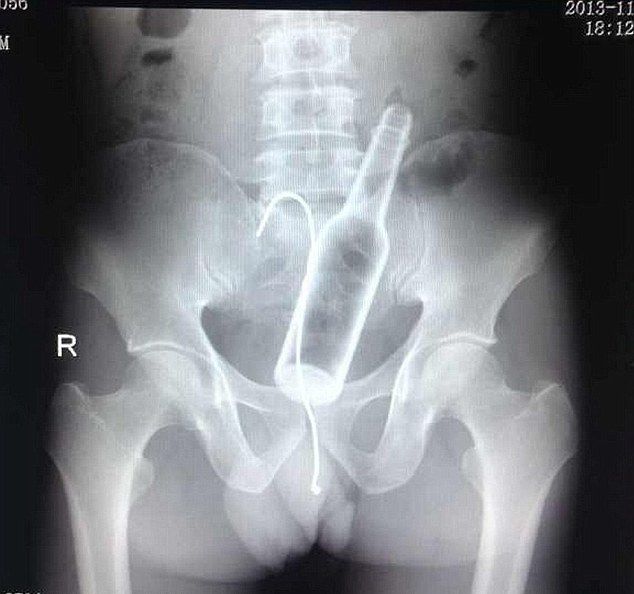

お尻の穴にビール瓶 ⇒ 抜けなくなって金属のワイヤーを突っ込む… レントゲン写真をご覧ください

gif_animation 中国・福建省の病院に、激しい腹痛を訴える1人の男性が現れた。事の顛末はこうだった。お尻の穴にビール瓶を入れ抜けなくなった彼はパニックになり、金属のワイヤー(フック)を突っ込みそれを取ろうと試みた。レントゲン写真。[3]images